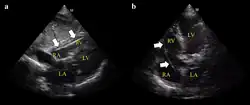

Configuração para fazer um ECG do dispositivo -

Exemplo de ECG do dispositivo a) flutuando livremente no VD b) em contato com a parede do VD -